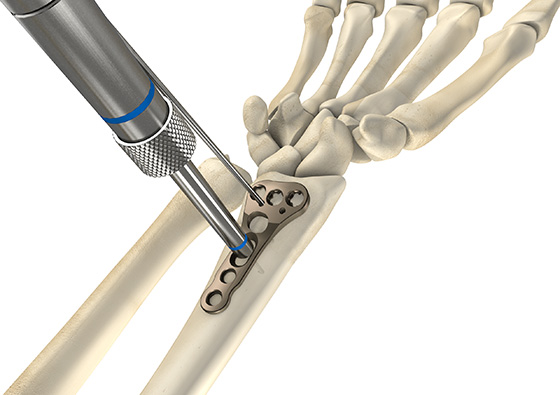

Distale Radiusplatte 3.5 Minor vws

Die distale Radiusplatte 3.5 Minor vws hat drei Löcher im Kopfbereich, jedoch einen schmalere Kopfbreite. Sie ist in winkelstabile und variabel winkelstabil erhältlich.

Mit der distalen Radiusplatte 3.5 Minor vws für die palmare Plattenosteosynthese können wie bei der Radiusplatte 3.5 Classic vws alle Radiusfrakturen operativ versorgt werden. Die anatomische Form der Platte wurde weiter verbessert und so ist sie im Kopfbereich schmaler als die Radiusplatte 3.5 Classic.

- Anatomisch angepasste Plattenform

- Unterschiedliche Plattenausführungen für links und rechts